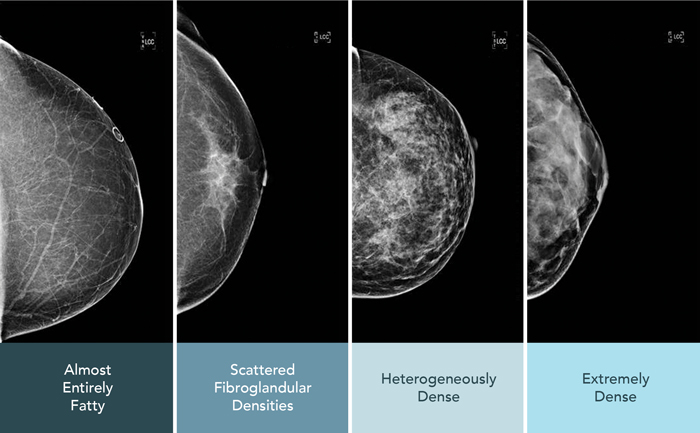

Everyone’s breasts are different. Some have more fat, others have more breast tissue. When there’s more breast tissue than fat, the breasts are considered dense.

- Dense tissue makes it harder to see cancer on a mammogram because both dense tissue and lumps appear white.